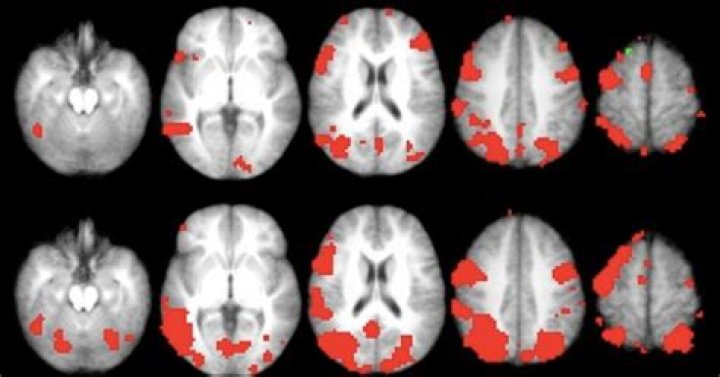

Your brain may remember something, even when you can't Even when a memory can't be accessed — that is, when it's forgotten — new research suggests it may persist in the brain. Researchers divide memories of events into two types: recollection and familiarity.

Why we forget seems to depend on how a memory is stored in the brain. Things we recollect are prone to interference. Things that feel familiar decay over time. The combination of both forgetting processes means that any message is unlikely to ever remain exactly the way you wrote it.

"Decades of research has shown that we have the ability to voluntarily forget something, but how our brains do that is still being questioned." Much prior research on intentional forgetting has focussed on brain activity in the prefrontal cortex, and the brain's memory centre, the hippocampus.

How traumatic memories are stored?

When a person experiences a traumatic event, adrenaline rushes through the body and the memory is imprinted into the amygdala, which is part of the limbic system. The memories are stored through fragments of visual images, smells, sounds, tastes, or touch.